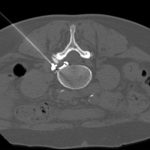

Согласно исследованию, опубликованному 28 марта в журнале «Радиология», импульсная радиочастота под контролем КТ в сочетании с инъекцией стероидов представляется многообещающей […]… далее